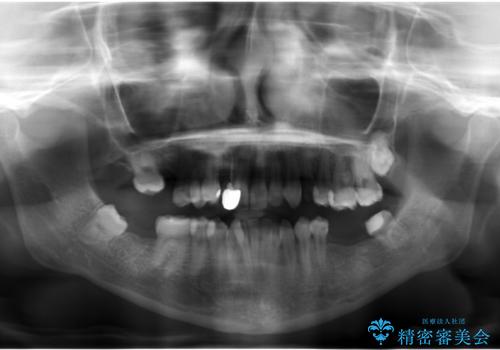

虫歯が多数、また奥歯も欠損してしまっていました。

左下の親知らず、左上の小臼歯が残根状態で一本抜いたほかは抜かずに矯正しました。

①保存不可能な歯は抜歯しそのすき間を矯正で閉じる

②右上の親知らずは活かしてブリッジの支台にする

という、予算がかからないように歯を保存する治療計画を立てました。

予算的に右下の一番奥のインプラントは難しかったため、できる限り対応しました。